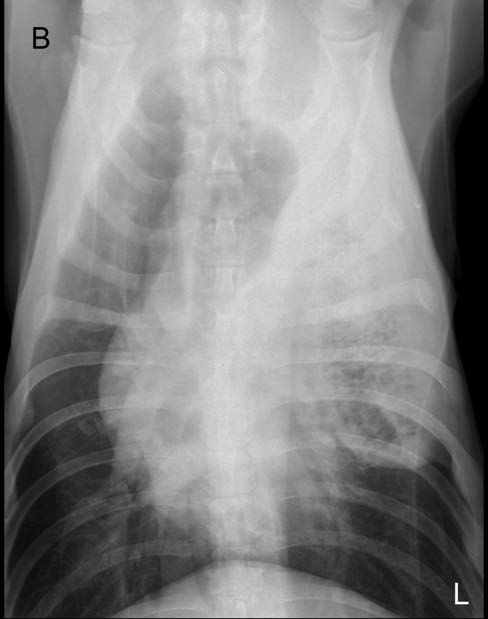

影像学检查

230只猫有X光片可供检查。其中70只(88.6%)猫被诊断为双侧积液,9只(11.4%)猫为单侧积液。不同组之间单侧或双侧积液的情况在统计学上无显著差异。

230只猫有X光检查报告,但仅79例能区分单侧或双侧积液。在有此信息的患者中,88.6%为双侧积液。这与大多数猫胸腔积液为双侧的假设相符,因为猫的胸膜腔是相通的。如果无法通过X光或超声确认,对于疑似胸腔积液的猫,盲目胸腔穿刺可能是一个不错的选择。积液可能在一侧更为明显,但通常两侧都会存在。